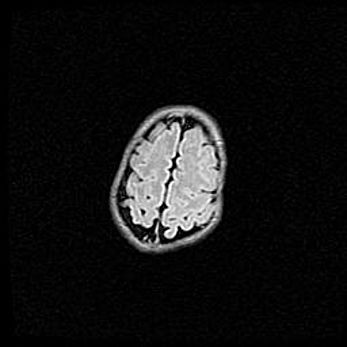

Аномалия Денди-Уокера. Признаки гипоплазии мозолистого тела.

Возраст: 5 месяцев 3 дня

Вес: 5550 г

Пол: мужской

Окружность головы: 39 см

Срок гестации: 40 недель

Аномалия Денди-Уокера – это порок развития головного мозга, для которого характерна триада симптомов: гипотрофия или аплазия червя мозжечка и/или полушарий мозжечка, расширение четвёртого желудочка с формированием ликворной кисты задней черепной ямки, гипертензионная гидроцефалия различной степени.

Гипоплазия мозолистого тела относится к дефектам внутриутробного этапа развития мозговой ткани, возникающим в процессе закладки структур головного мозга, что происходит на начальных этапах развития эмбриона.